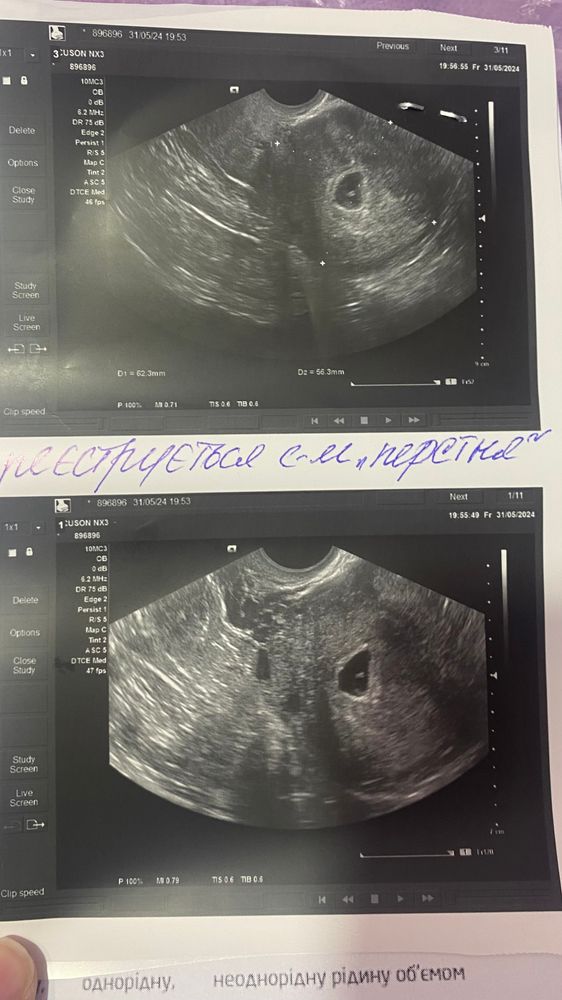

Появился эмбриончик,доктор написала «синдром перстня» (позавчера его не видели),но ктр не измерили и сердцебиения нет пока,к сожалению( жм позавчера был 3,8 сегодня-3,4 не знаю уменьшается ли он или это погрешность узи. Пя было позавчера 9,01мм, сегодня-11,9мм( на 5 недель и 3 дня,по факту-6,1, овуляция отслежена,сегодня 31дпо)

сказали,если в течении этой недели не будет сердцебиения,то можно не надеяться уже(